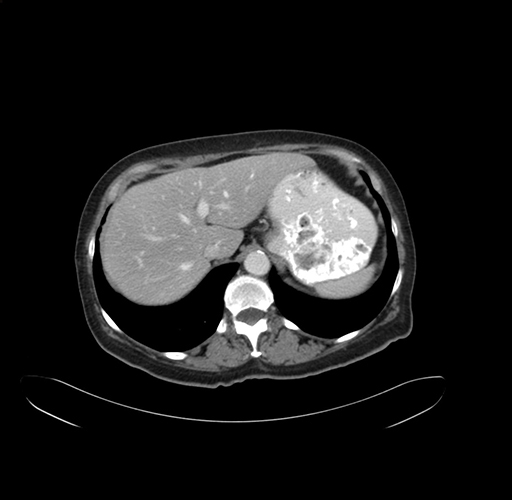

Pre-Chemo: Axial Venous

Axial Venous